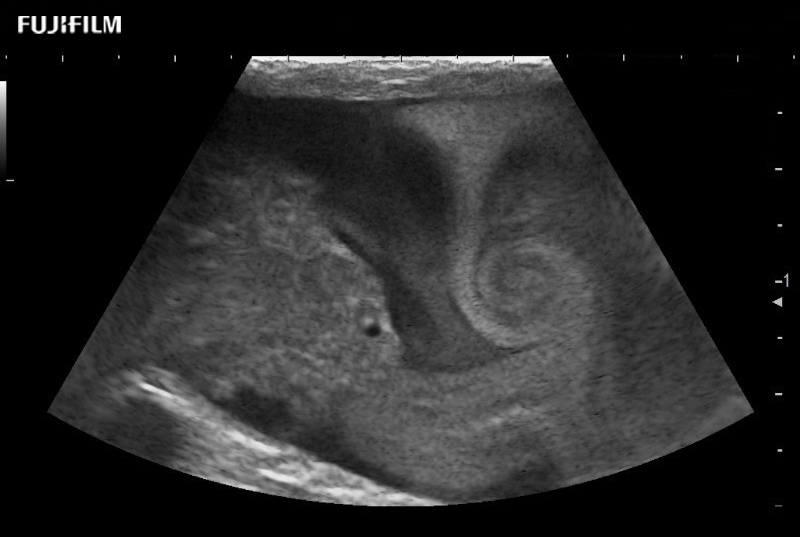

The ARIETTA 750 incorporates all of the proven technologies and functions that medical professionals have come to expect from Fujifilm Healthcare.

ARIETTA 750 is the definitive diagnostic ultrasound solution for any clinical setting - Private Office, Imaging Center, or Hospital. The ARIETTA platform provides the ultimate in clinical performance with its state-of-the-art features and large user-friendly display.

The ARIETTA 650 DI combines trusted Fujifilm Healthcare technologies and features tailored for surgical oncology.

Designed to meet the demands of surgeons, the ARIETTA 650 DI offers precise guidance. Its advanced capabilities and large, intuitive display offer accurate and efficient care in operating rooms and specialized surgical settings.